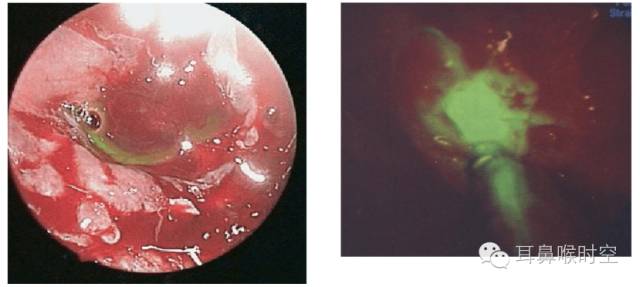

鼻内镜检查:无创、直观(漏口定位)

鼻内镜检查

顶前部→顶后部→蝶筛隐窝→中鼻道→咽鼓管咽口 。

局部黏膜水肿或肉芽、息肉。

检查每个部位时,可压迫双侧颈内静脉,颅内压增高,观察脑脊液从何处流入鼻腔。

鞘内注射荧光素

优点:定位精确

缺点:有创伤性,精确定位需要暴露颅底

自发性脑脊液鼻漏

左:筛顶漏伴有鼻息肉 右:筛板漏

脑膜眶膨出与筛顶缺损

垂体瘤术后蝶窦漏